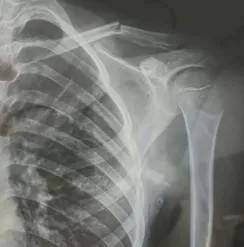

10月30日,内蒙古自治区赤峰市宁城县苏木皋小学一学生家长贾女士给记者打来电话,介绍了孩子被打的原因币安官方网站。贾女士称,放学通道的墙上有一个电灯的开关,好多孩子放学时都随手去拨弄开关。出于安全考虑,学校和老师都禁止孩子拨弄开关。23日放学时,他儿子和另一个同学调皮,再去拨弄了那个开关,被正在值班的另一个班的班主任发现,把她儿子打了,且打骨折了。

图片由报料者提供